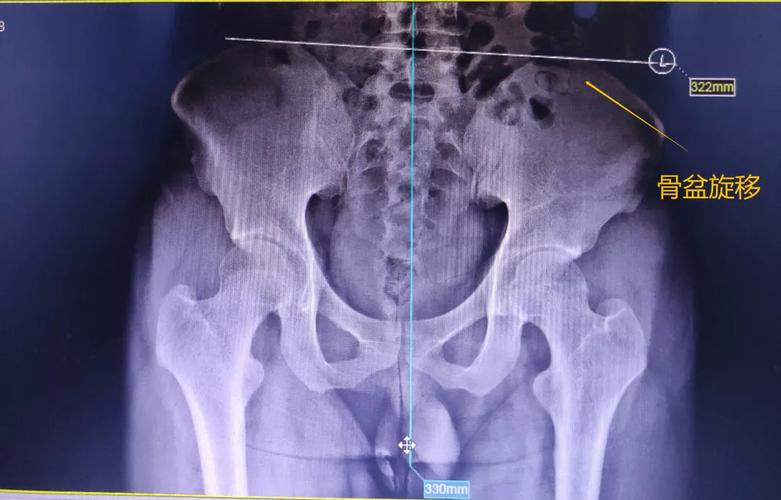

4. 骨盆旋转

体态与疼痛系列文章之骨盆旋转

有一种腰腿疼痛叫骨盆旋移症!

骨盆旋转图片